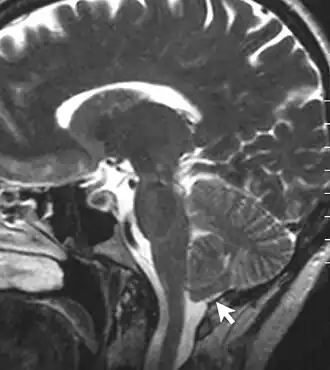

![]() Imagen radiográfica de una persona con malformación de Chiari tipo I. Una parte del cerebelo (amígdala cerebelosa), ha descendido 7 mm por debajo del foramen magno (agujero occipital). | ||

Si las amígdalas cerebelosas son empujadas al canal medular sin involucrar al tallo cerebral, se considera que la Chiari es del tipo I. Afortunadamente,[8] ya que es el tipo más frecuente. Normalmente solo se diagnostica en la adultez, durante un examen dirigido a diagnosticar otras patologías. Todas las Chiari adquiridas o secundarias pertenecen exclusivamente al tipo I.[8]

Las malformaciones de Chiari tipo I pueden, no obstante, obstruir el flujo de líquido cefalorraquídeo y comprimir la médula espinal. Algunas veces están asociadas a la siringomielia.